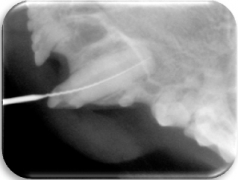

- Radiográfico (analógico y digital)

El diagnóstico clínico oral es de suma importancia ya que el plan de tratamiento y el pronóstico dependen de un certero y profundo análisis de los signos de la cavidad oral. Nuestra principal preocupación es atender los problemas que se encuentran en cavidad oral pero además siempre realizamos un detallado análisis de la función general del paciente. En nuestro centro revisamos de manera general a la mascota detectando cualquier problema sistémico. Contamos con un laboratorio de análisis clínicos en donde se realizan biometría hemática, química sanguínea, examen general de orina y pruebas para detección de enfermedades virales y de otros microorganismos. Contamos también con un laboratorio de histopatología en donde se revisa el material biológico para la detección y el diagnóstico de cambios morfológicos y lesiones en los tejidos. En lo que respecta al diagnóstico de la boca, contamos con un expediente donde se vacía toda la información dental y bucal de tal manera que mantenemos el control del tratamiento odontológico desde el inicio hasta el final y en donde el propietario o el médico que nos recomienda puede revisar en detalle toda la información recabada. Contamos con todo el instrumental y el equipo necesario para el diagnóstico de el aparato estomatognático (cavidad oral con dientes, tejidos de sostén y tejidos blandos, además de las estructuras relacionadas como articulación temporomandibular, cavidad nasal, cavidad orbitaria, etc.). Contamos con luz similar a la ultravioleta para diagnóstico de lesiones dentales por transluminación, pulpómetro para diagnóstico de vitalidad pulpar, localizador de ápices para tratamiento de conductos y equipo radiográfico tanto analógico como digital.